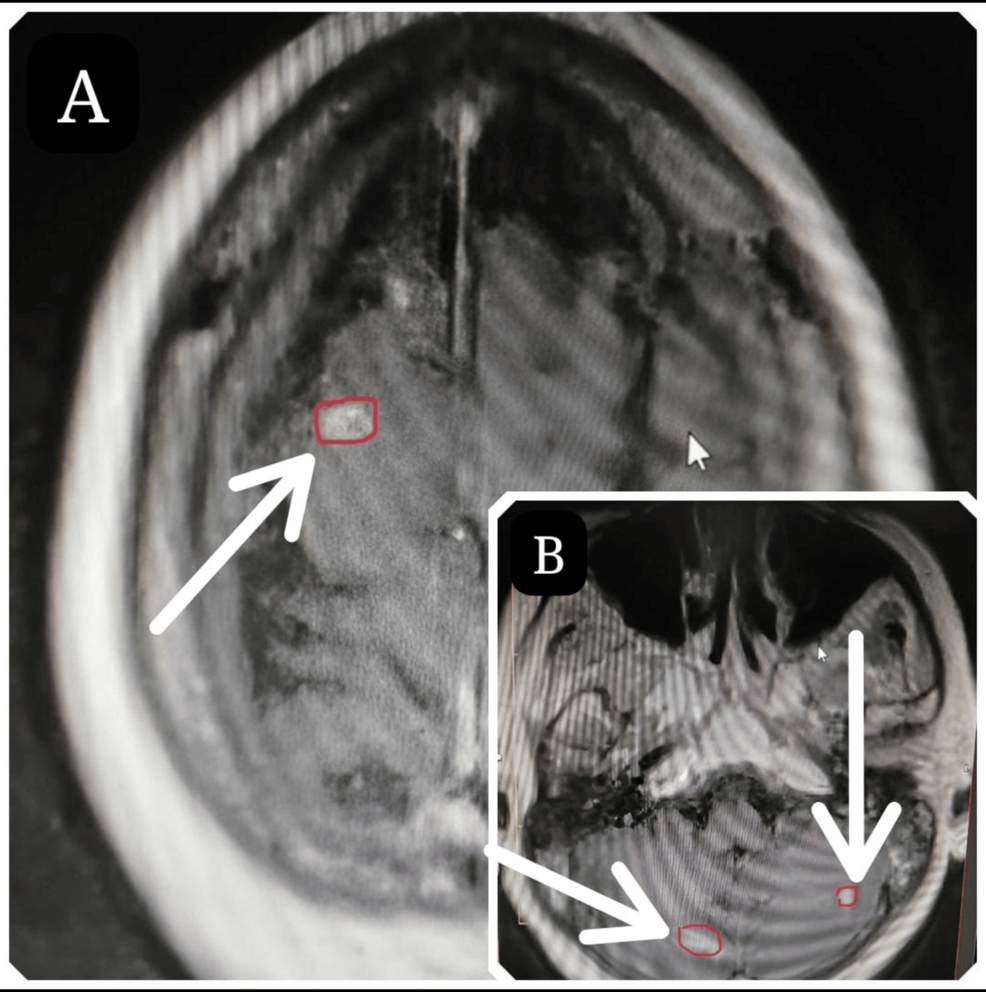

She complained of a headache for three months; however, no neurological deficits were noticeable upon examination. Further workup was suggestive of stage IV BrCA with metastases in the brain. Neuro-navigation-guided MRI of the brain was suggestive of multiple variable-sized cortical, subcortical, and intra-axial enhancing brain lesions in bilateral cerebral hemispheres and posterior fossa. The largest two lesions in the right frontal lobe and right cerebellum measured 12.5 × 14 × 9.4 mm and 13 × 17 × 12 mm, respectively. A neuro-navigation-guided biopsy of the frontal lesion was performed to confirm receptor status and was still suggestive of triple-negative metastatic invasive ductal carcinoma.

A team meeting was conducted at our center with a neuroradiologist mapping 60 lesions of BMs at various locations (Video 1). The patient was classified as Eastern Cooperative Oncology Group performance status scale 0 and prepared for frameless stereotactic CyberKnife radiosurgery using Accuray Precision version 33.13(2). We chose this approach considering her comorbidities, profession, and to avoid escalating neuro-cognitive dysfunction (owing to her age and prior WBRT).